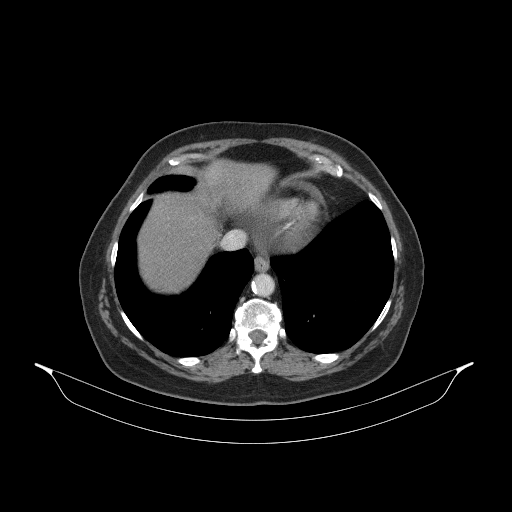

Original VENOUS CT scan

Full window (WL 1023.5, WW 4095 β†’ Low βˆ’1024, High +3071)

Actual HU range: [-160.0, 240.0]

Lung window (WL -600, WW 1500 β†’ Low βˆ’1350, High +150)

Actual HU range: [-160.0, 150.0]

Mediastinum window (WL 40, WW 400 β†’ Low βˆ’160, High +240)